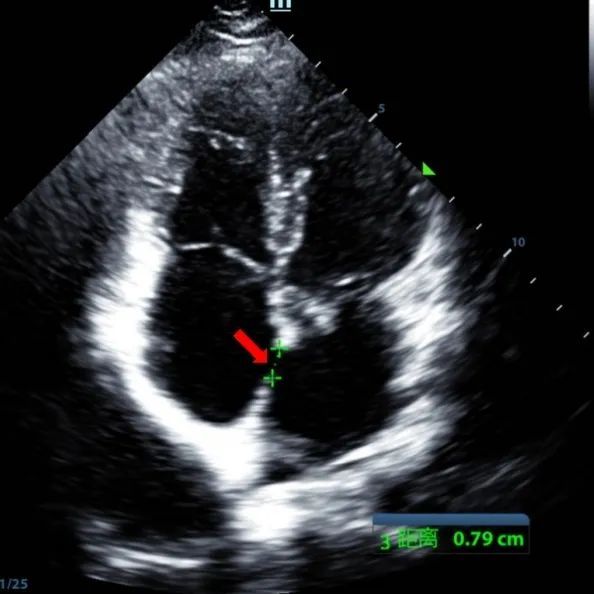

Un garçon de 9 ans avec un TSA secundum (7,5-7,9mm) a été traité à l'aide d'un occulteur MemoSorb BDASD-I 12mm et d'un système d'administration 12F. Aucune complication ou comorbidités n'a été notée avant l'intervention.

Serial echocardiographic follow-ups showed stable device position and favorable cardiac remodeling. Gradual degradation confirmed the occluder's long-term safety and efficacy.